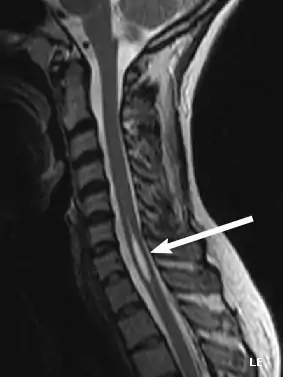

Physicians now use magnetic resonance imaging (MRI) to diagnose syringomyelia. The MRI radiographer takes images of body anatomy, such as the brain and spinal cord, in vivid detail. This test will show the syrinx in the spine or any other conditions, such as the presence of a tumor. MRI is safe, painless, and informative and has greatly improved the diagnosis of syringomyelia.[14][15][16][17][18][19][20][21][22][23][24][25]

The possible causes are trauma, tumors, and congenital defects. It is most usually observed in the part of the spinal cord corresponding to the neck area. Symptoms are due to spinal cord damage and include pain, decreased sensation of touch, weakness, and loss of muscle tissue. The diagnosis is confirmed with a spinal CT, myelogram or MRI of the spinal cord. The cavity may be reduced by surgical decompression.